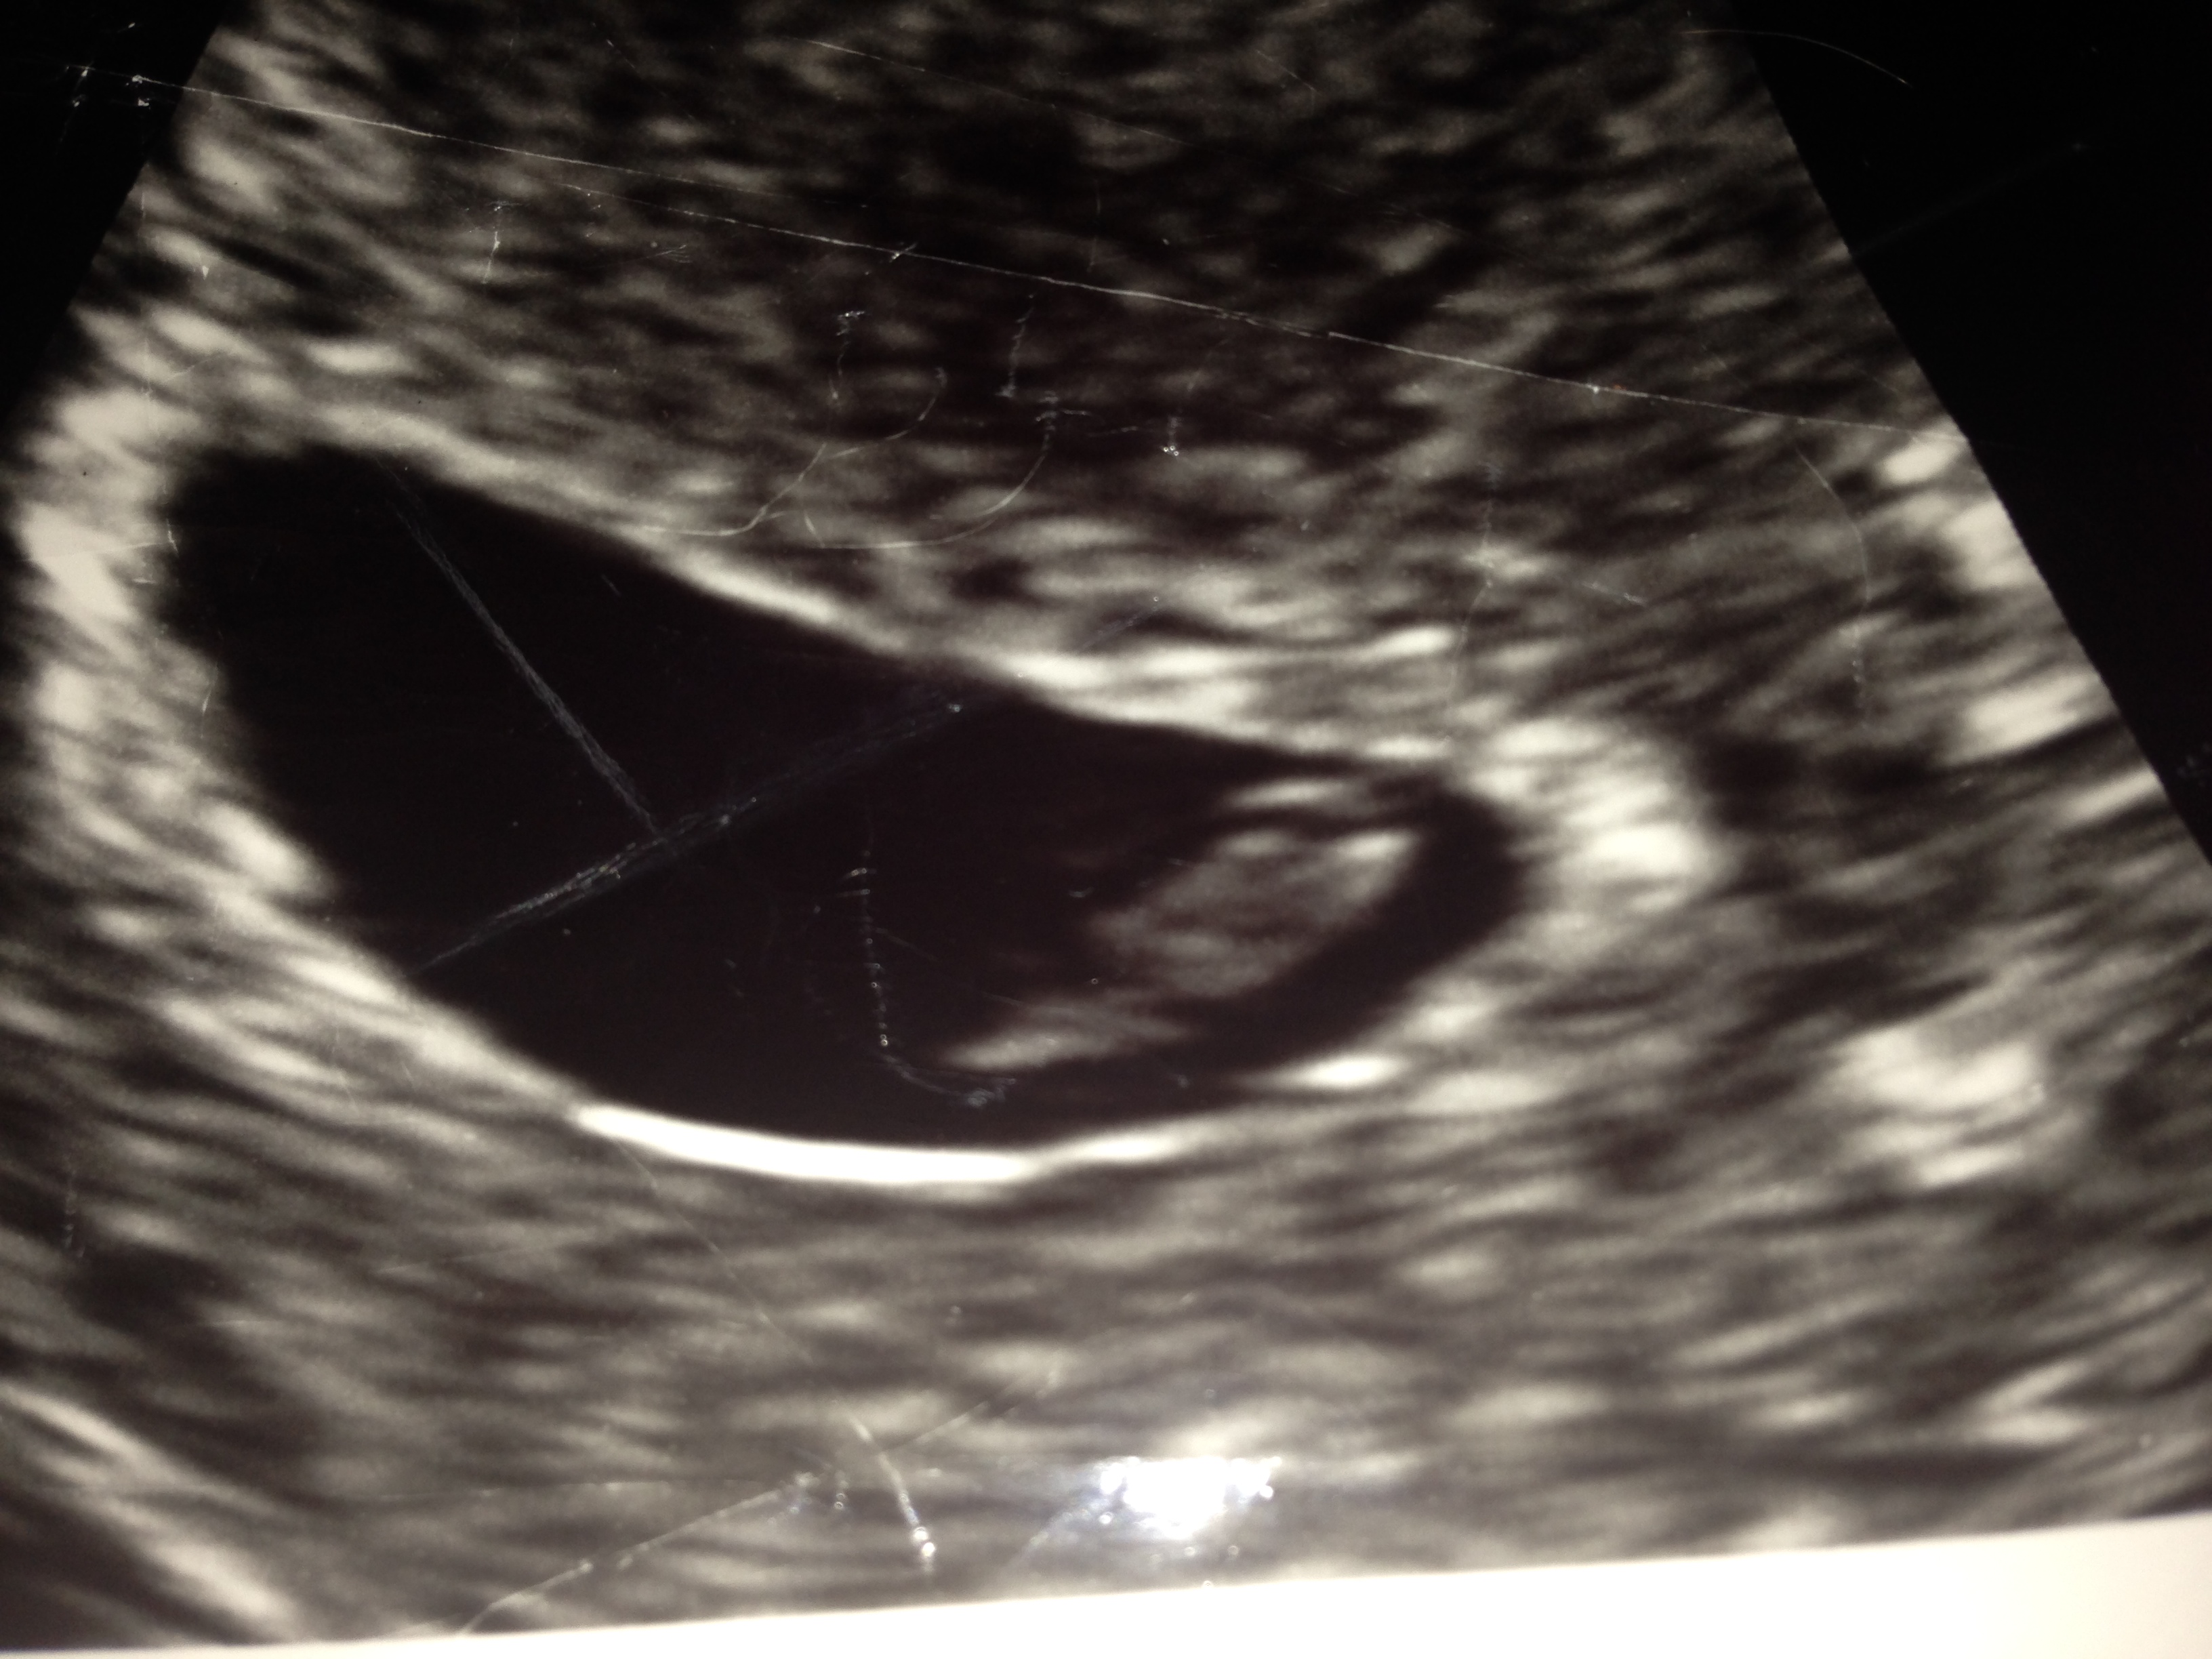

Baby Blip

This was Gavin as an Embryo being carefully placed into my womb. He looked like a little blip on the screen and we referred to him as Baby Blip from that time on.